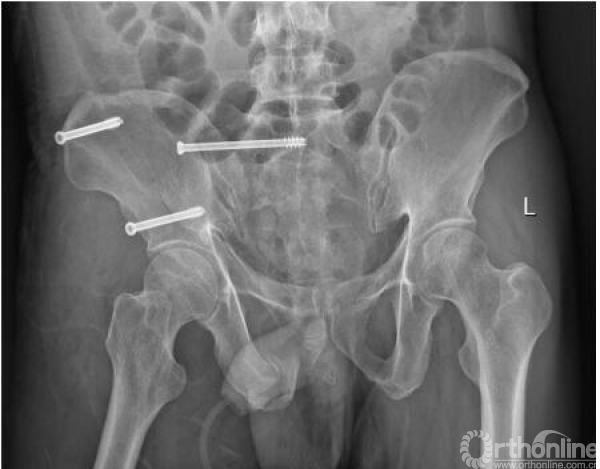

术后复查影像(2017.09.28、2017.10.05)

术后x线(2017.09.17)

骨盆正位、骨盆入口位、骨盆出口位